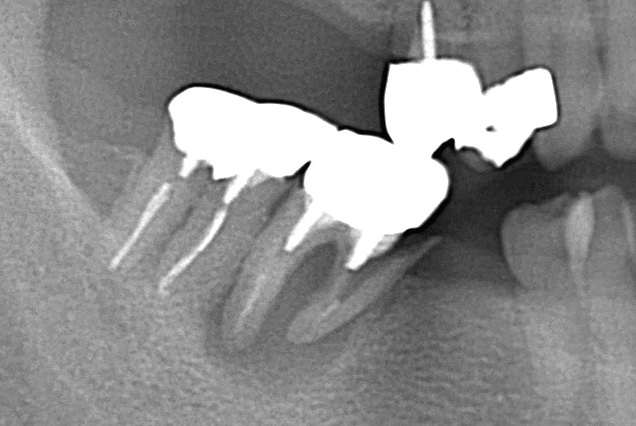

●金属の被せ物で、歯の頭の部分は補強できても根の部分は補強できない

神経の治療をした歯は、残った部分を補強するために金属セラミックなどの丈夫な素材の被せ物をします。しかし被せ物で補強できるのは歯ぐきの上の歯の頭部分だけで、その下の歯の根の部分は補強できません。

●金属の土台が入っているとクサビの力がかかる

神経の治療をした歯でも、特に金属の土台が入っている歯は歯が割れるリスクが高くなります。金属の土台は歯よりも固く、噛む力が加わるたびに歯に対してくさびのような力がかかります。それが繰り返されることにより、金属の土台との境目から歯が割れやすくなります。